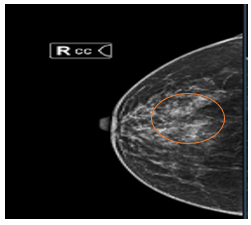

- Xquang tuyến vú: Vú phải vị trí 1/4 trên ngoài có hình ảnh đám tăng đậm độ bất xứng khu trú, bên trong có nốt vôi hóa đa hình rõ (BIRADS4). Hiện không thấy bất thường tuyến vú trái trên Xquang (BIRADS 1)

Hình 1:

Hình Xquang tuyến vú: Vú phải vị trí 1/4 trên ngoài có hình ảnh đám tăng đậm độ bất xứng khu trú, bên trong có nốt vôi hóa đa hình rõ (vòng tròn màu cam).